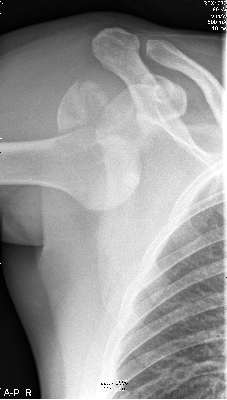

Na de ongelukige val was de arm uit de kom. |

|